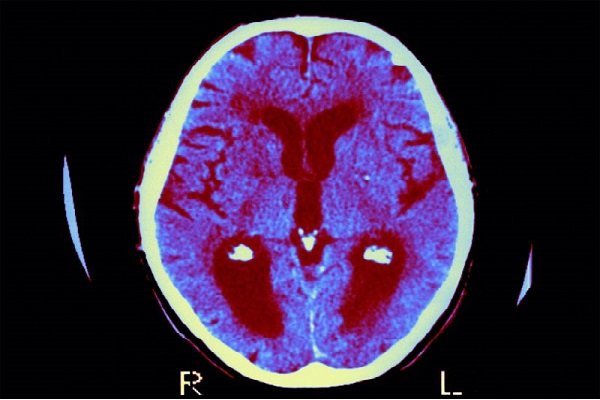

بر اساس یک مطالعه جدید، قرار گرفتن در معرض سرب در دوران بارداری و اوایل کودکی ممکن است سرعت فراموشی اطلاعات در کودکان را افزایش دهد و به طور بالقوه یادگیری و رشد شناختی را مختل کند.

این مطالعه نشان داد که سطح بالاتر سرب خون بین سنین ۴ تا ۶ سال، حتی در سطوح نسبتاً پایین مواجهه، به طور قابل توجهی با سرعت بیشتر فراموشی مرتبط است، به طوری که میانگین سطح سرب خون تقریباً ۱.۷ میکروگرم در دسی‌لیتر است.

این یافته‌ها نشان می‌دهد که حتی مواجهه با سرب در سطوح پایین نیز می‌تواند عملکردهای شناختی حیاتی را در اوایل کودکی به خطر بیندازد.